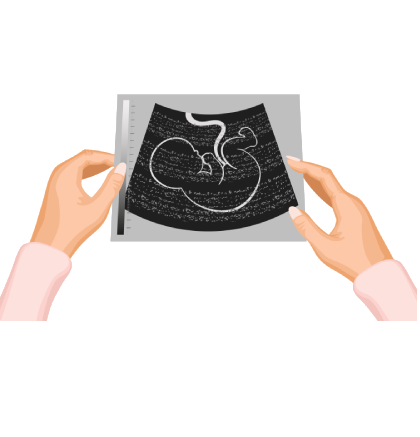

7.What are the things done during antenatal care?

Antenatal care generally consists of periodical checkups and counseling, ultrasound scans, healthy dietary care, a supply of proper vitamins to the body and regular exercise for a healthy delivery. The recommendation may vary based on your unique circumstances.